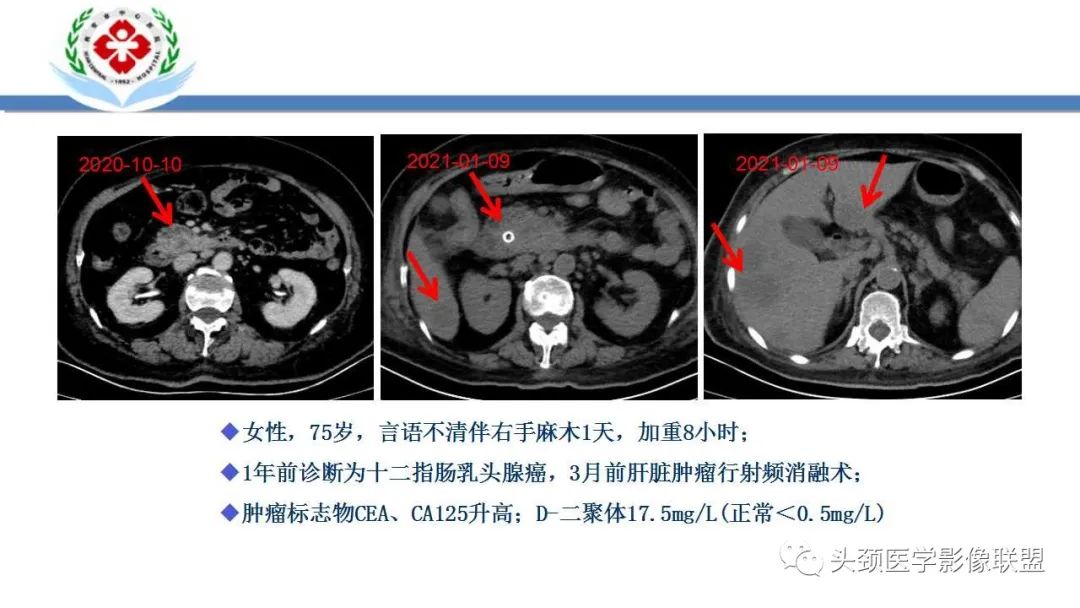

原发肿瘤部位多为肺,其次为胰腺、消化道、肾脏、卵巢和前列腺(腺癌和黏液癌);是一种副肿瘤综合征,一旦形成即提示预后不良(中位生存期约为4.5m);反复缺血性脑卒中是Trousseau综合征的一种表现形式,容易被临床忽视。